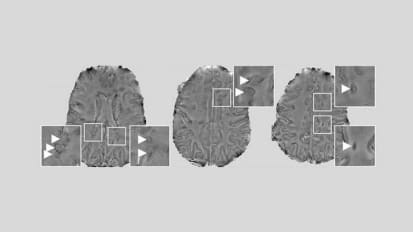

Researchers Identify Inflamed Brain Cells Likely Involved in MS Nerve Degeneration

MRI scans of a patient’s brain showing the chronic active lesions (areas of localized damage marked by arrows within magnified insets) associated with multiple sclerosis (MS). Johns Hopkins Medicine and National Institute of Neurological ...